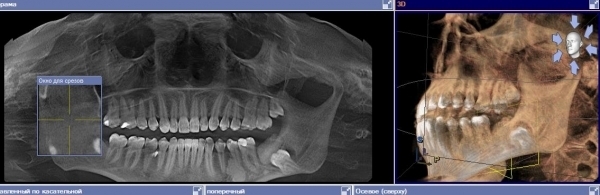

В десне, где должен был вылезти зуб мудрости, появилась дырка, и из нее виден зуб. Пошла к хирургу-стоматологу, сделали ортопантомограмму. Оказалось, это не зуб, а какое-то костное образование, а зуб сидит на челюсти. Из дырки в десне что-то выделяется, похожее на кровь.

Необходимо удалить обе ретинированные восьмёрки (28, 38), и именно в зачатке, не дожидаясь прорастания. Так как по снимку наблюдается воспалительный процесс в области этих зубов. А также, однозначно, произойдёт скученность всего зубного ряда, по причине недостатка места.

Вам необходим грамотный челюстно-лицевой хирург для качественной манипуляции. Не дожидайтесь обострений и болезненных ощущений.